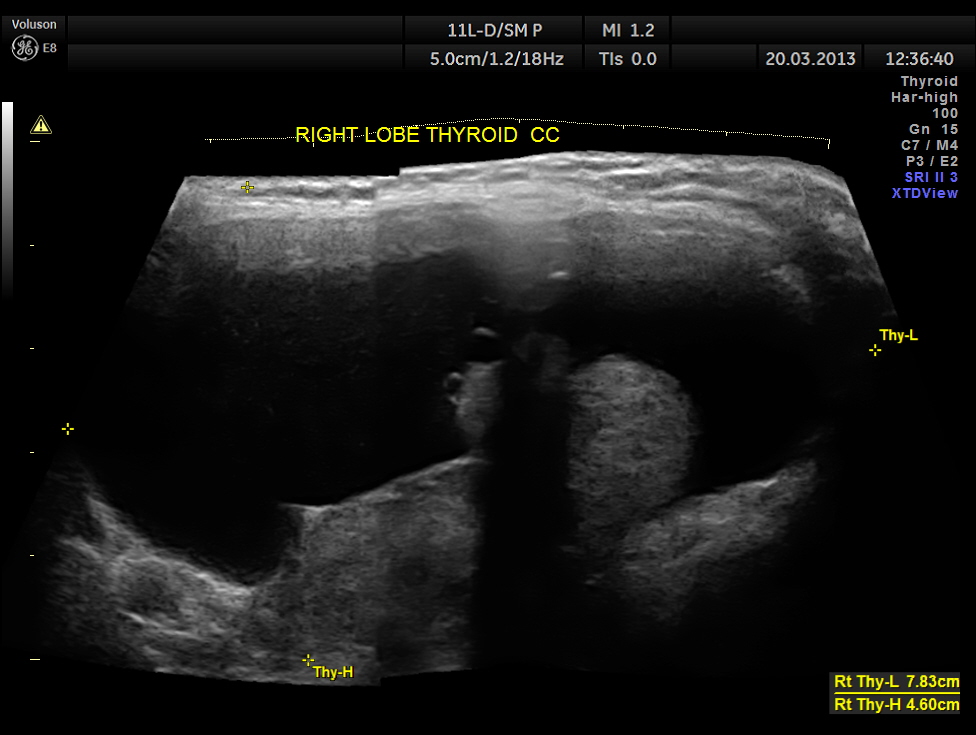

This was a 50 year old lady who was evaluated for thyromegaly.

The right lobe of the thyroid was grossly enlarged , with predominantly cystic appearance , with eccentric solid tissue, with prominently increased vascularity in the solid portion.